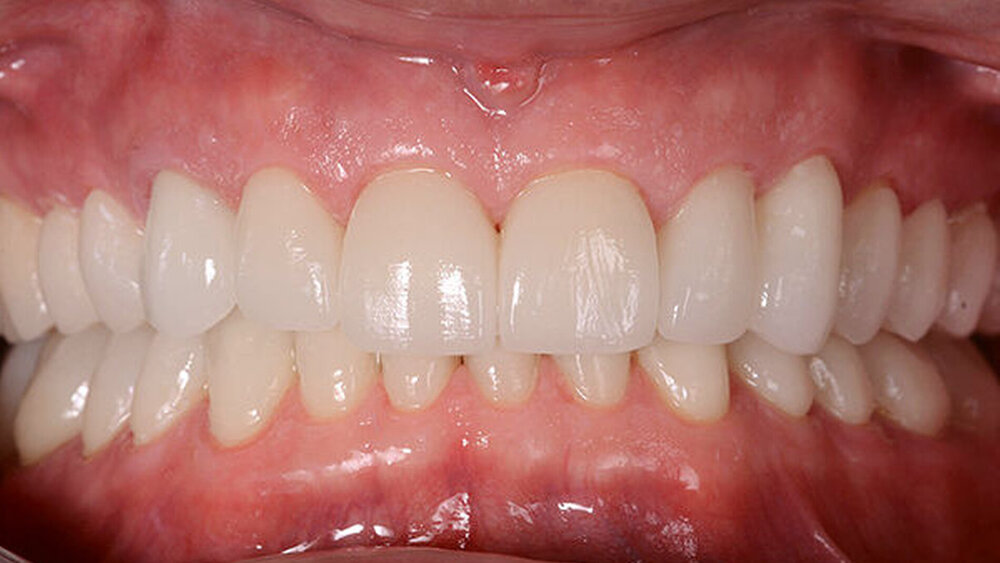

Die Kronen (11–13, 21–23) und Veneers (14, 15, 16, 17, 24, 25, 26, 27, 31, 32, 33, 34, 35, 36, 37, 41, 42, 43, 44, 45, 46, 47) wurden mit einem lichthärtenden, polymerisierenden Harz‧adhäsiv (Futurabond U und Bifix QM; VOCO) an den Abutments befestigt. Zur Polymerisation wurde ein Hochleistungs-LED-Lichthärtegerät verwendet (Celalux 3; VOCO), siehe die Abbildungen 11 und 12.

Überschüssiges Befestigungsmaterial wurde entfernt und Anpassungen der Okklusion wurden vorgenommen und mit der T-Scan-Technologie (TeK-scan) überprüft. Zum Schutz der endgültigen Restaurationen wurde eine abnehmbare Acrylschiene angefertigt. Nach 6 Monaten wurden die endgültigen Restaurationen überprüft. Sie waren noch immer stabil und wiesen keine Frakturspuren auf (Abb. 13–15). Der Patient berichtete zudem, dass er mit der neuen Bisshöhe keine Kopfschmerzen mehr hatte.